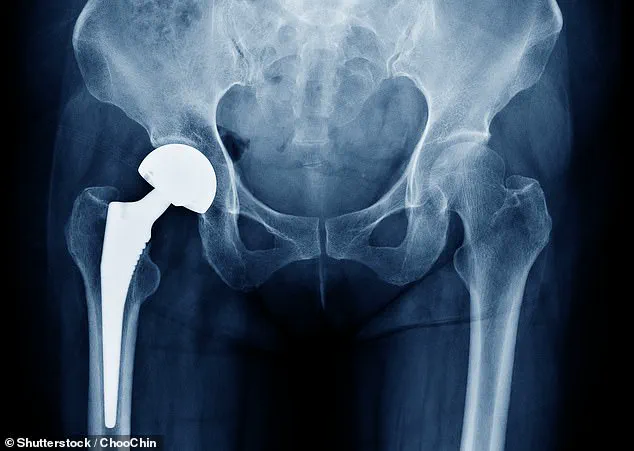

Urgent Warning: Thousands of British Patients Face Health Risks Due to Hip Implant Malfunction, Says MHRA